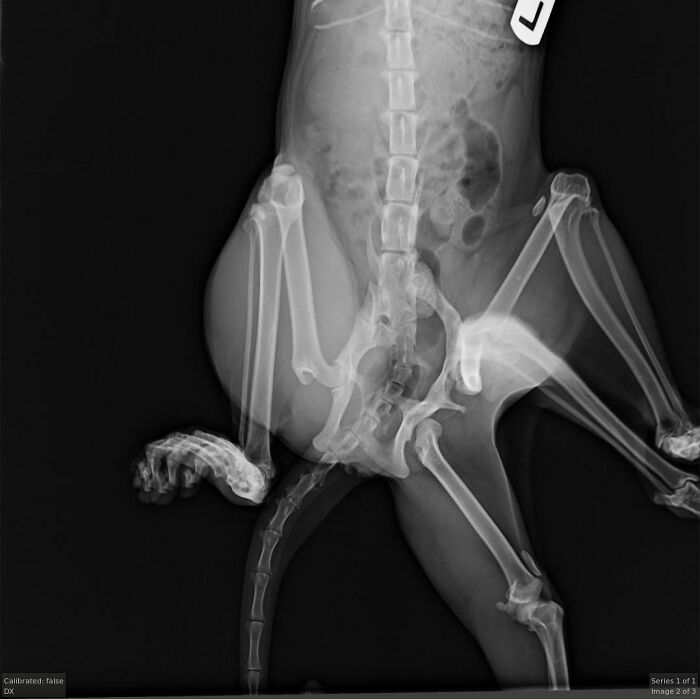

This is Bitsy, a cat born with a very rare condition

While in the womb, she absorbed a littermate, which caused her to have two extra legs and a second pelvis as she grew

At Windermere Veterinary Hospital, vets took X-rays and decided surgery was the best way to help Bitsy live more comfortably